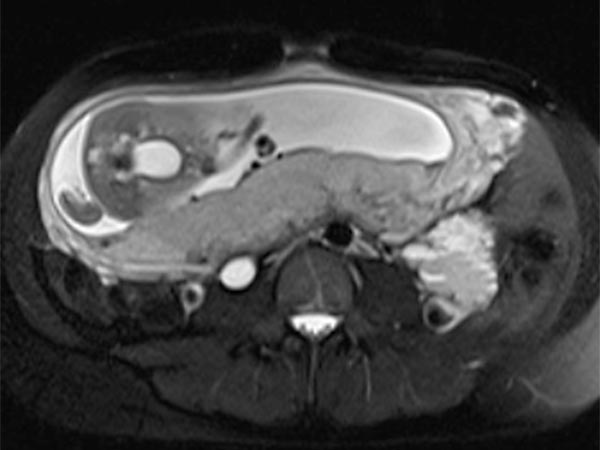

Coronal (top) and axial (bottom) T2-weighted, fat-suppressed MR sequences without contrast at baseline before pregnancy.

An intraabdominal venous malformation (VM) diagnosed as an incidental finding is monitored on MRI during the patient's pregnancy.

T2-weighted sequences without contrast on a 1.5T MRI scanner allow for follow-up without endangering the fetus.